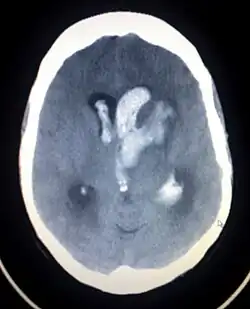

An intracranial hemorrhage, one cause of altered level of consciousness